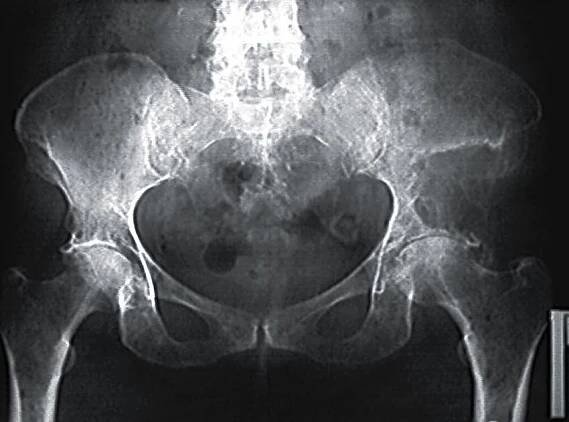

Kyčelní kloub je největší kloub v lidském těle a je tvořen spojením kosti stehenní s kostí pánevní. Je to kloub jednoduchý, tedy složený pouze ze dvou kostí, ale díky silným vazům, které kostní spojení obklopují, zároveň také nejpevnější.

Náhrada kyčle patří v současné době k nejčastějším operačním výkonům v ortopedii. Je metodou volby u pacientů s pokročilým stupněm artrózy (III. a vyšší stupeň), po zlomeninách krčku a nekrózy hlavice stehenní kosti.